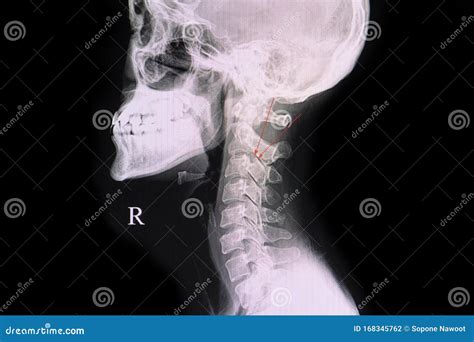

In diagnostic imaging, the pedicle of a vertebra is a key landmark. Radiologists use X-rays, CT scans, and MRI to visualize the pedicle and assess its integrity. Any abnormalities in the pedicle, such as fractures or tumors, can indicate underlying spinal pathologies.

The pedicle of a vertebra is a short, thick process that extends from the vertebral body to the lamina. It forms part of the vertebral arch, which encloses the spinal canal. The pedicle is a key structural element that connects the vertebral body to the posterior elements of the vertebra, including the lamina, spinous process, and transverse processes.

• Shape and Size: The pedicle is typically cylindrical or oval in shape and varies in size depending on the level of the vertebra. Cervical pedicles are smaller, while lumbar pedicles are larger and stronger.